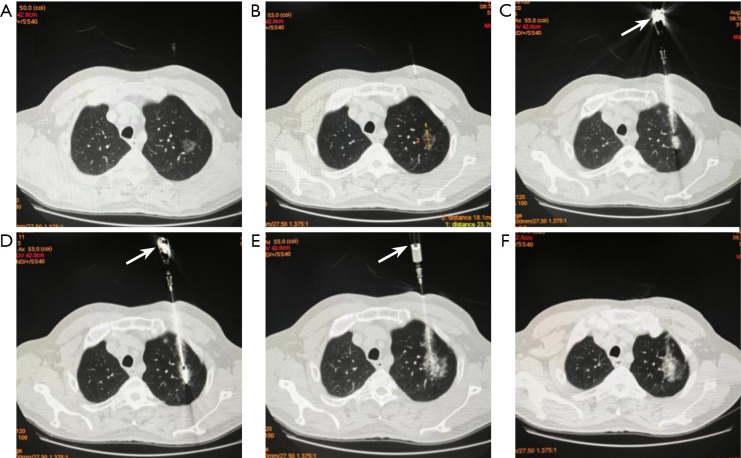

Methods: From January 2021 to December 2024, 91 patients with single highly suspected malignant PNs underwent synchronous MWA combined with PB. A total of 56 patients in group A underwent synchronous MWA followed by PB (MWA-first group) and 35 cases in group B underwent synchronous PB followed by MWA (PB-first group). The technical success, pathologically positive diagnosis rate, complications, and efficacy of the two groups were compared.

Results: The differences in technical success rate (100% vs. 97.1%) and positive pathologic diagnosis rate (80.4% vs. 88.6%) between group A and group B were not statistically significant (P>0.05). The most common complications included pneumothorax, intrapulmonary hemorrhage, hemoptysis, and pleural effusion. The incidence of intrapulmonary hemorrhage was significantly lower in group A than in group B (19.6% vs. 42.8%, P<0.05). The median follow-up time was 18.0 months, the local control rate was 98.8%, and the complete ablation (CA) rate was 56.6%.

Conclusions: Synchronous MWA combined with PB is a safe and effective strategy. MWA followed by PB could reduce the impact of intrapulmonary hemorrhage on ablation outcomes and is an alternative treatment for highly suspected malignant PN.